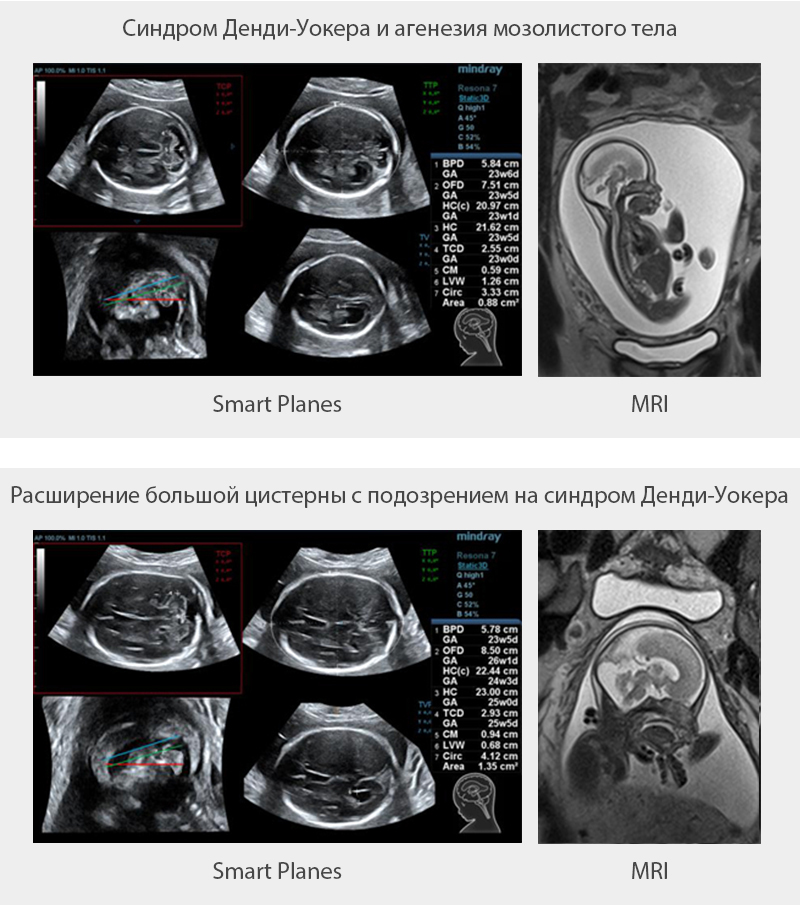

Smart Planes

–С–ї–∞–≥–Њ–і–∞—А—П —Г–љ–Є–Ї–∞–ї—М–љ–Њ–є –љ–Њ–≤–∞—В–Њ—А—Б–Ї–Њ–є —В–µ—Е–љ–Њ–ї–Њ–≥–Є–Є –Ї–Њ–Љ–њ–∞–љ–Є–Є Mindray, —Б–Є—Б—В–µ–Љ–∞ Resona 6 —П–≤–ї—П–µ—В—Б—П –љ–Њ–≤–µ–є—И–µ–є —Б–Є—Б—В–µ–Љ–Њ–є —Г–ї—М—В—А–∞–Ј–≤—Г–Ї–Њ–≤—Л—Е –Є—Б—Б–ї–µ–і–Њ–≤–∞–љ–Є–є, –Њ–±–µ—Б–њ–µ—З–Є–≤–∞—О—Й–µ–є –њ–Њ–ї–љ–Њ—Б—В—М—О –∞–≤—В–Њ–Љ–∞—В–Є—З–µ—Б–Ї–Њ–µ –Є —В–Њ—З–љ–Њ–µ –њ–Њ–ї—Г—З–µ–љ–Є–µ –Њ—Б–Њ–±–Њ –≤–∞–ґ–љ—Л—Е –њ—А–Њ–µ–Ї—Ж–Є–є –Є –њ—А–Њ–≤–µ–і–µ–љ–Є–µ –љ–∞–Є–±–Њ–ї–µ–µ —З–∞—Б—В–Њ –Є—Б–њ–Њ–ї—М–Ј—Г–µ–Љ—Л—Е –Є–Ј–Љ–µ—А–µ–љ–Є–є –¶–Э–° –њ–ї–Њ–і–∞, —З—В–Њ –Њ–±—Г—Б–ї–Њ–≤–ї–Є–≤–∞–µ—В –Є–љ—В–µ–ї–ї–µ–Ї—В—Г–∞–ї—М–љ—Г—О –і–Є–∞–≥–љ–Њ—Б—В–Є–Ї—Г, —Г–ї—Г—З—И–µ–љ–Є–µ –њ—А–Њ–Є–Ј–≤–Њ–і–Є—В–µ–ї—М–љ–Њ—Б—В–Є –Є —Б–љ–Є–ґ–µ–љ–Є–µ –Ј–∞–≤–Є—Б–Є–Љ–Њ—Б—В–Є –Њ—В –њ–Њ–ї—М–Ј–Њ–≤–∞—В–µ–ї—П.

Smart Planes вАФ —Н—В–Њ —Г–і–Њ–±–љ—Л–є –і–ї—П –њ–Њ–ї—М–Ј–Њ–≤–∞—В–µ–ї—П –Є–љ—Б—В—А—Г–Љ–µ–љ—В, –Ј–љ–∞—З–Є—В–µ–ї—М–љ–Њ –њ–Њ–≤—Л—И–∞—О—Й–Є–є —Н—Д—Д–µ–Ї—В–Є–≤–љ–Њ—Б—В—М —Б–Ї–∞–љ–Є—А–Њ–≤–∞–љ–Є—П –Ј–∞ —Б—З–µ—В —Г–≤–µ–ї–Є—З–µ–љ–Є—П —В–Њ—З–љ–Њ—Б—В–Є –≤ —Б–Њ—З–µ—В–∞–љ–Є–Є —Б –∞–≤—В–Њ–Љ–∞—В–Є–Ј–∞—Ж–Є–µ–є —А–∞–±–Њ—В—Л. –Ю–і–љ–Њ–≥–Њ –љ–∞–ґ–∞—В–Є—П –љ–∞ –Ї–ї–∞–≤–Є—И—Г –і–Њ—Б—В–∞—В–Њ—З–љ–Њ, —З—В–Њ–±—Л –Є–Ј 3D –і–∞–љ–љ—Л—Е, –њ–Њ–ї—Г—З–µ–љ–љ—Л—Е –њ—А–Є —Б–Ї–∞–љ–Є—А–Њ–≤–∞–љ–Є–Є –Љ–Њ–Ј–≥–∞ –њ–ї–Њ–і–∞, –љ–µ–Љ–µ–і–ї–µ–љ–љ–Њ –њ–Њ–ї—Г—З–Є—В—М —Б—В–∞–љ–і–∞—А—В–љ—Л–µ –њ–ї–Њ—Б–Ї–Њ—Б—В–Є —Б–Ї–∞–љ–Є—А–Њ–≤–∞–љ–Є—П –¶–Э–°: MSP (–Љ–µ–і–Є–∞–ї—М–љ–∞—П —Б–∞–≥–Є—В—В–∞–ї—М–љ–∞—П –њ–ї–Њ—Б–Ї–Њ—Б—В—М), TCP (—В—А–∞–љ—Б—Ж–µ—А–µ–±—А–∞–ї—М–љ–∞—П –њ–ї–Њ—Б–Ї–Њ—Б—В—М), TTP (—В—А–∞–љ—Б—В–∞–ї–∞–Љ–Є—З–µ—Б–Ї–∞—П –њ–ї–Њ—Б–Ї–Њ—Б—В—М) –Є TVP (—В—А–∞–љ—Б–≤–µ–љ—В—А–Є–Ї—Г–ї—П—А–љ–∞—П –њ–ї–Њ—Б–Ї–Њ—Б—В—М), –∞ —В–∞–Ї–ґ–µ –њ–Њ–ї—Г—З–∞–µ–Љ—Л–µ –≤ –љ–Є—Е –Є–Ј–Љ–µ—А–µ–љ–Є—П (–С–Я–†, –Ю–У, –Ы–Ч–†, –Я–Њ–њ–µ—А–µ—З–љ—Л–є –Ф–Є–∞–Љ–µ—В—А –Ь–Њ–Ј–ґ–µ—З–Ї–∞, –С–Њ–ї—М—И–∞—П –¶–Є—Б—В–µ—А–љ–∞ –Є –®–Є—А–Є–љ–∞ –С–Њ–Ї–Њ–≤–Њ–≥–Њ –Ц–µ–ї—Г–і–Њ—З–Ї–∞).